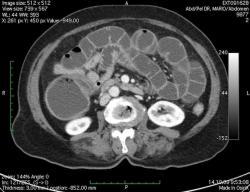

КТ брюшной полости. Женщина 73 года с жалобами на запоры.

Пациентка женщина 73 года. Предъявляет жалобы на запоры, спастические боли в брюшной полости.

ИзображениеЦиркулярное сужение в поперечной ободочной кишке. Ни это ли причина проблемм?

Новообразование в среднем отделе поперечной ободочной кишки с циркулярным сужением просвета и хронической механической толстокишечной непроходимостью. Признаков метастазирования в данной анатомической области не обнаружено. Пациент безусловно нуждается в хирургическом лечении.

Я не занимаюсь КТ, но сам характер сужения толстой кишки как-то вызывает сомнения, ракового ли он характера? Сужение то циркулярное, но больно уж ровненькое и нет признаков инфильтрации вокруг (хотя рак, конечно может иметь и такой вид). Ну, думаю dr.Mario со временем откроет карты и будет дана гистология.

Циркулярная стенозирующая опухоль (аденокарцнома) толстого кишечника; с типичной КТ презентацией и признаками обструкции. Пациентка была оперирована на второй день после КТ.